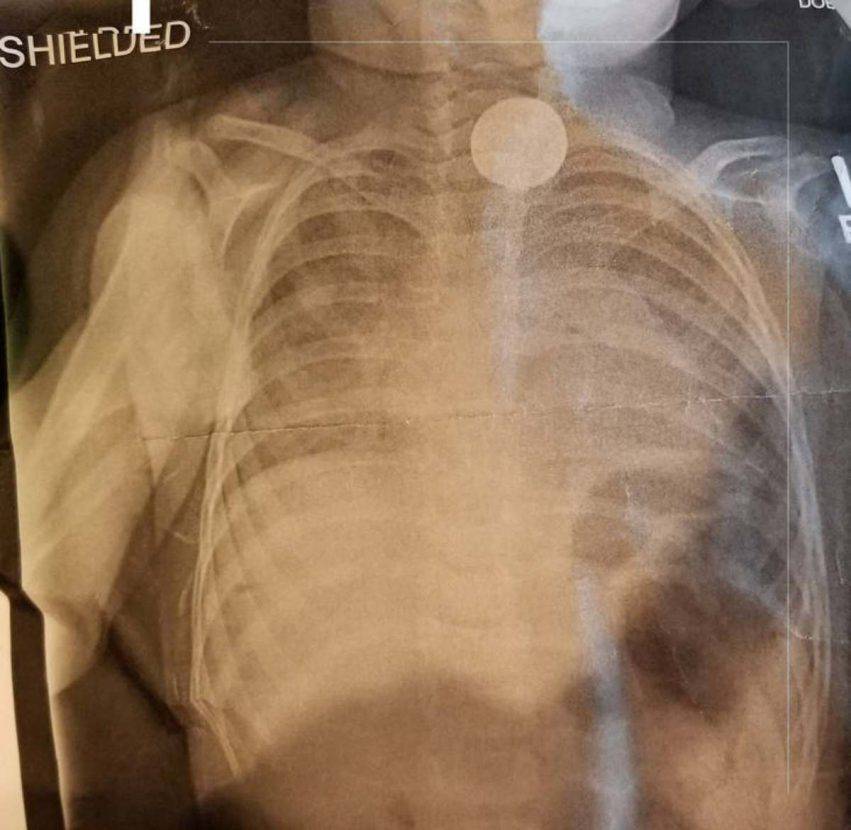

I raggi X hanno mostrato un oggetto circolare che i medici ritenevano fosse una moneta.

Quando la bimba ha iniziato a vomitare pezzi anneriti i sospetti si sono fatti più forti: Abigayle aveva ingerito una batteria.

La bimba è stata operata d’urgenza per rimuovere la batteria e cercare di limitare i danni all’esofago.